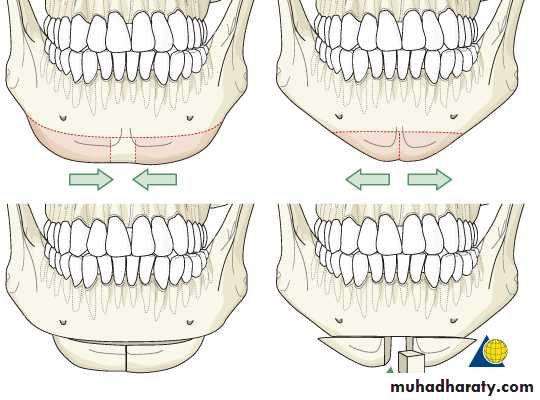

Correction of mandibular retrusion. Usually can be combined with genioplasty carried out simultaneously, alternative procedure for mandibular advancement are the inverted L osteotomy and C ramus osteotomy.Correction of mandibular protrusion (prognathism).if the set back movement is graeter than 20 mm bimaxillary surgery should be considerd.

Correction of mandibular asymetry. Usually can be done bilaterally (BSSO) and combined with maxillary osteotomy ( bimaxillary surgery)